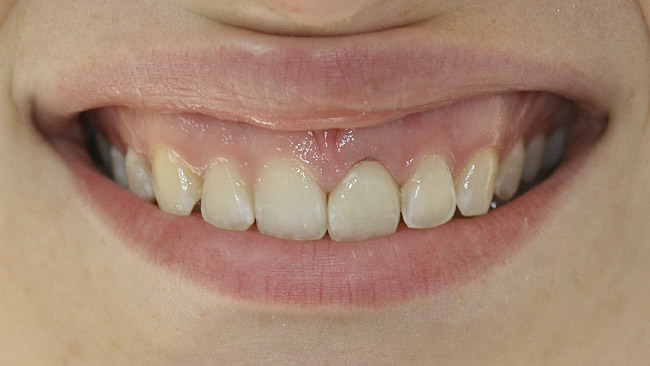

For the provisional implant crown, the restorative dentist relined a clear acrylic, vacuum-formed stent with bis-acryl and picked up the plastic sleeve packaged with the immediate temporary abutment. A convex subgingival profile was contoured to gently support the FGM circumferentially. The provisional crown was then cemented with non-eugenol-based temporary cement (Figure 18 and Figure 19).

The restorative dentist observed that the implant-retained temporary crown on No. 9 was slightly wider mesiodistally than No. 8 due to a slight midline discrepancy (Figure 19). Composite resin was added to the mesial aspect of No. 8, balancing the mesiodistal width, effecting a better tooth-size match, and providing cosmetic correction of the midline by moving it slightly to the left. The cement-retained bis-acryl provisional was maintained out of occlusion; this strategy was changed to light occlusion in protrusive for the final crown, and is in agreement with cautionary notes by Vermylen et al regarding porcelain stress arising from excessive occlusion (particularly in excursive movements) and compromised chewing with lack of occlusion.12

Figure 19  Bis-acryl provisional crown placed by restorative dentist (facial view).

Figure 19